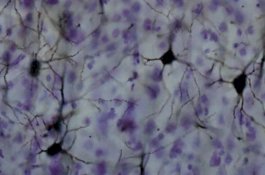

Mandi di Sumber Air Panas, Pria Ini Nyaris Tewas karena Bakteri Pemakan Otak